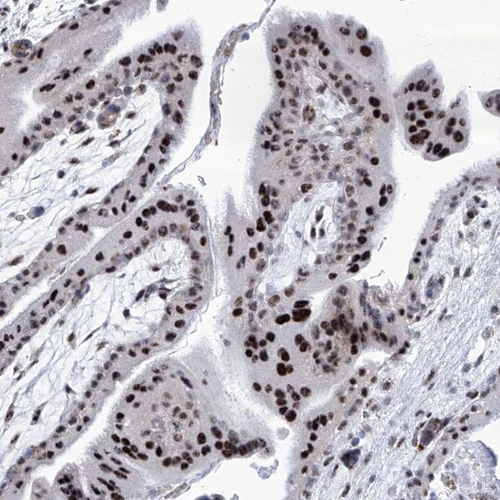

Immunohistochemical staining of human placenta shows strong nuclear positivity in trophoblastic cells.